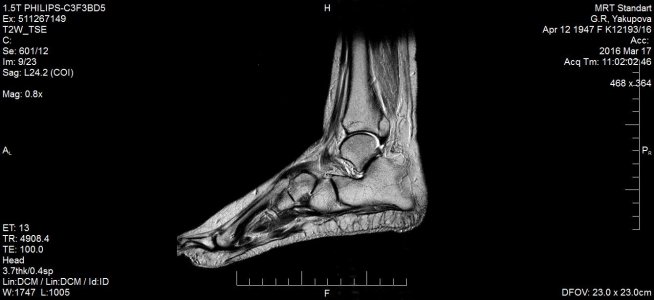

16 марта МРТ заключение: МР- картина консолидирующегося краевого косого перелома дорзальных отделов медиальной лодыжки /без смещения - перелом пилона тип В1 по АО/; остеоартроза голеностопного сустава и стопы: минимального синовита голеностопного сустава. Признаки отека мягких тканей области голеностопного сустава. (фото № 2)